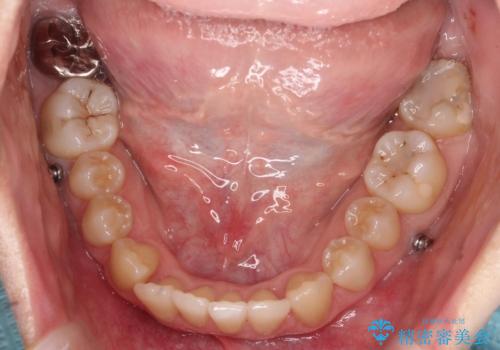

- 前歯のデコボコ(叢生)と、前歯が上下逆の咬み合わせ(反対咬合)を主訴にご来院されました。精密検査の結果、歯列全体のスペースが不足していることが判明。患者様のご希望に合わせ、透明で目立ちにくい**インビザライン(マウスピース矯正)**による治療計画を立案しました。歯を抜かずに、歯列全体を奥(遠心)へ移動させることで、歯が並ぶスペースを確保し、叢生と反対咬合を同時に改善することを目指します。

今回の矯正治療では、透明なマウスピース型の装置インビザラインを使用しました。この装置は目立たず、取り外しが可能なため、食事や歯磨きも普段通り行えます。治療は、緻密な治療計画に基づき、段階的に作製されたマウスピースを交換していくことで、遠心移動という方法で奥歯から徐々に歯列全体を後方へ動かしました。これにより、不足していたスペースを確保し、前歯のデコボコを解消。同時に、上下の歯の前後的な関係を改善することで、反対咬合も正常な咬み合わせへと導きました。見た目も機能も改善し、自然で美しい笑顔を獲得していただけました。